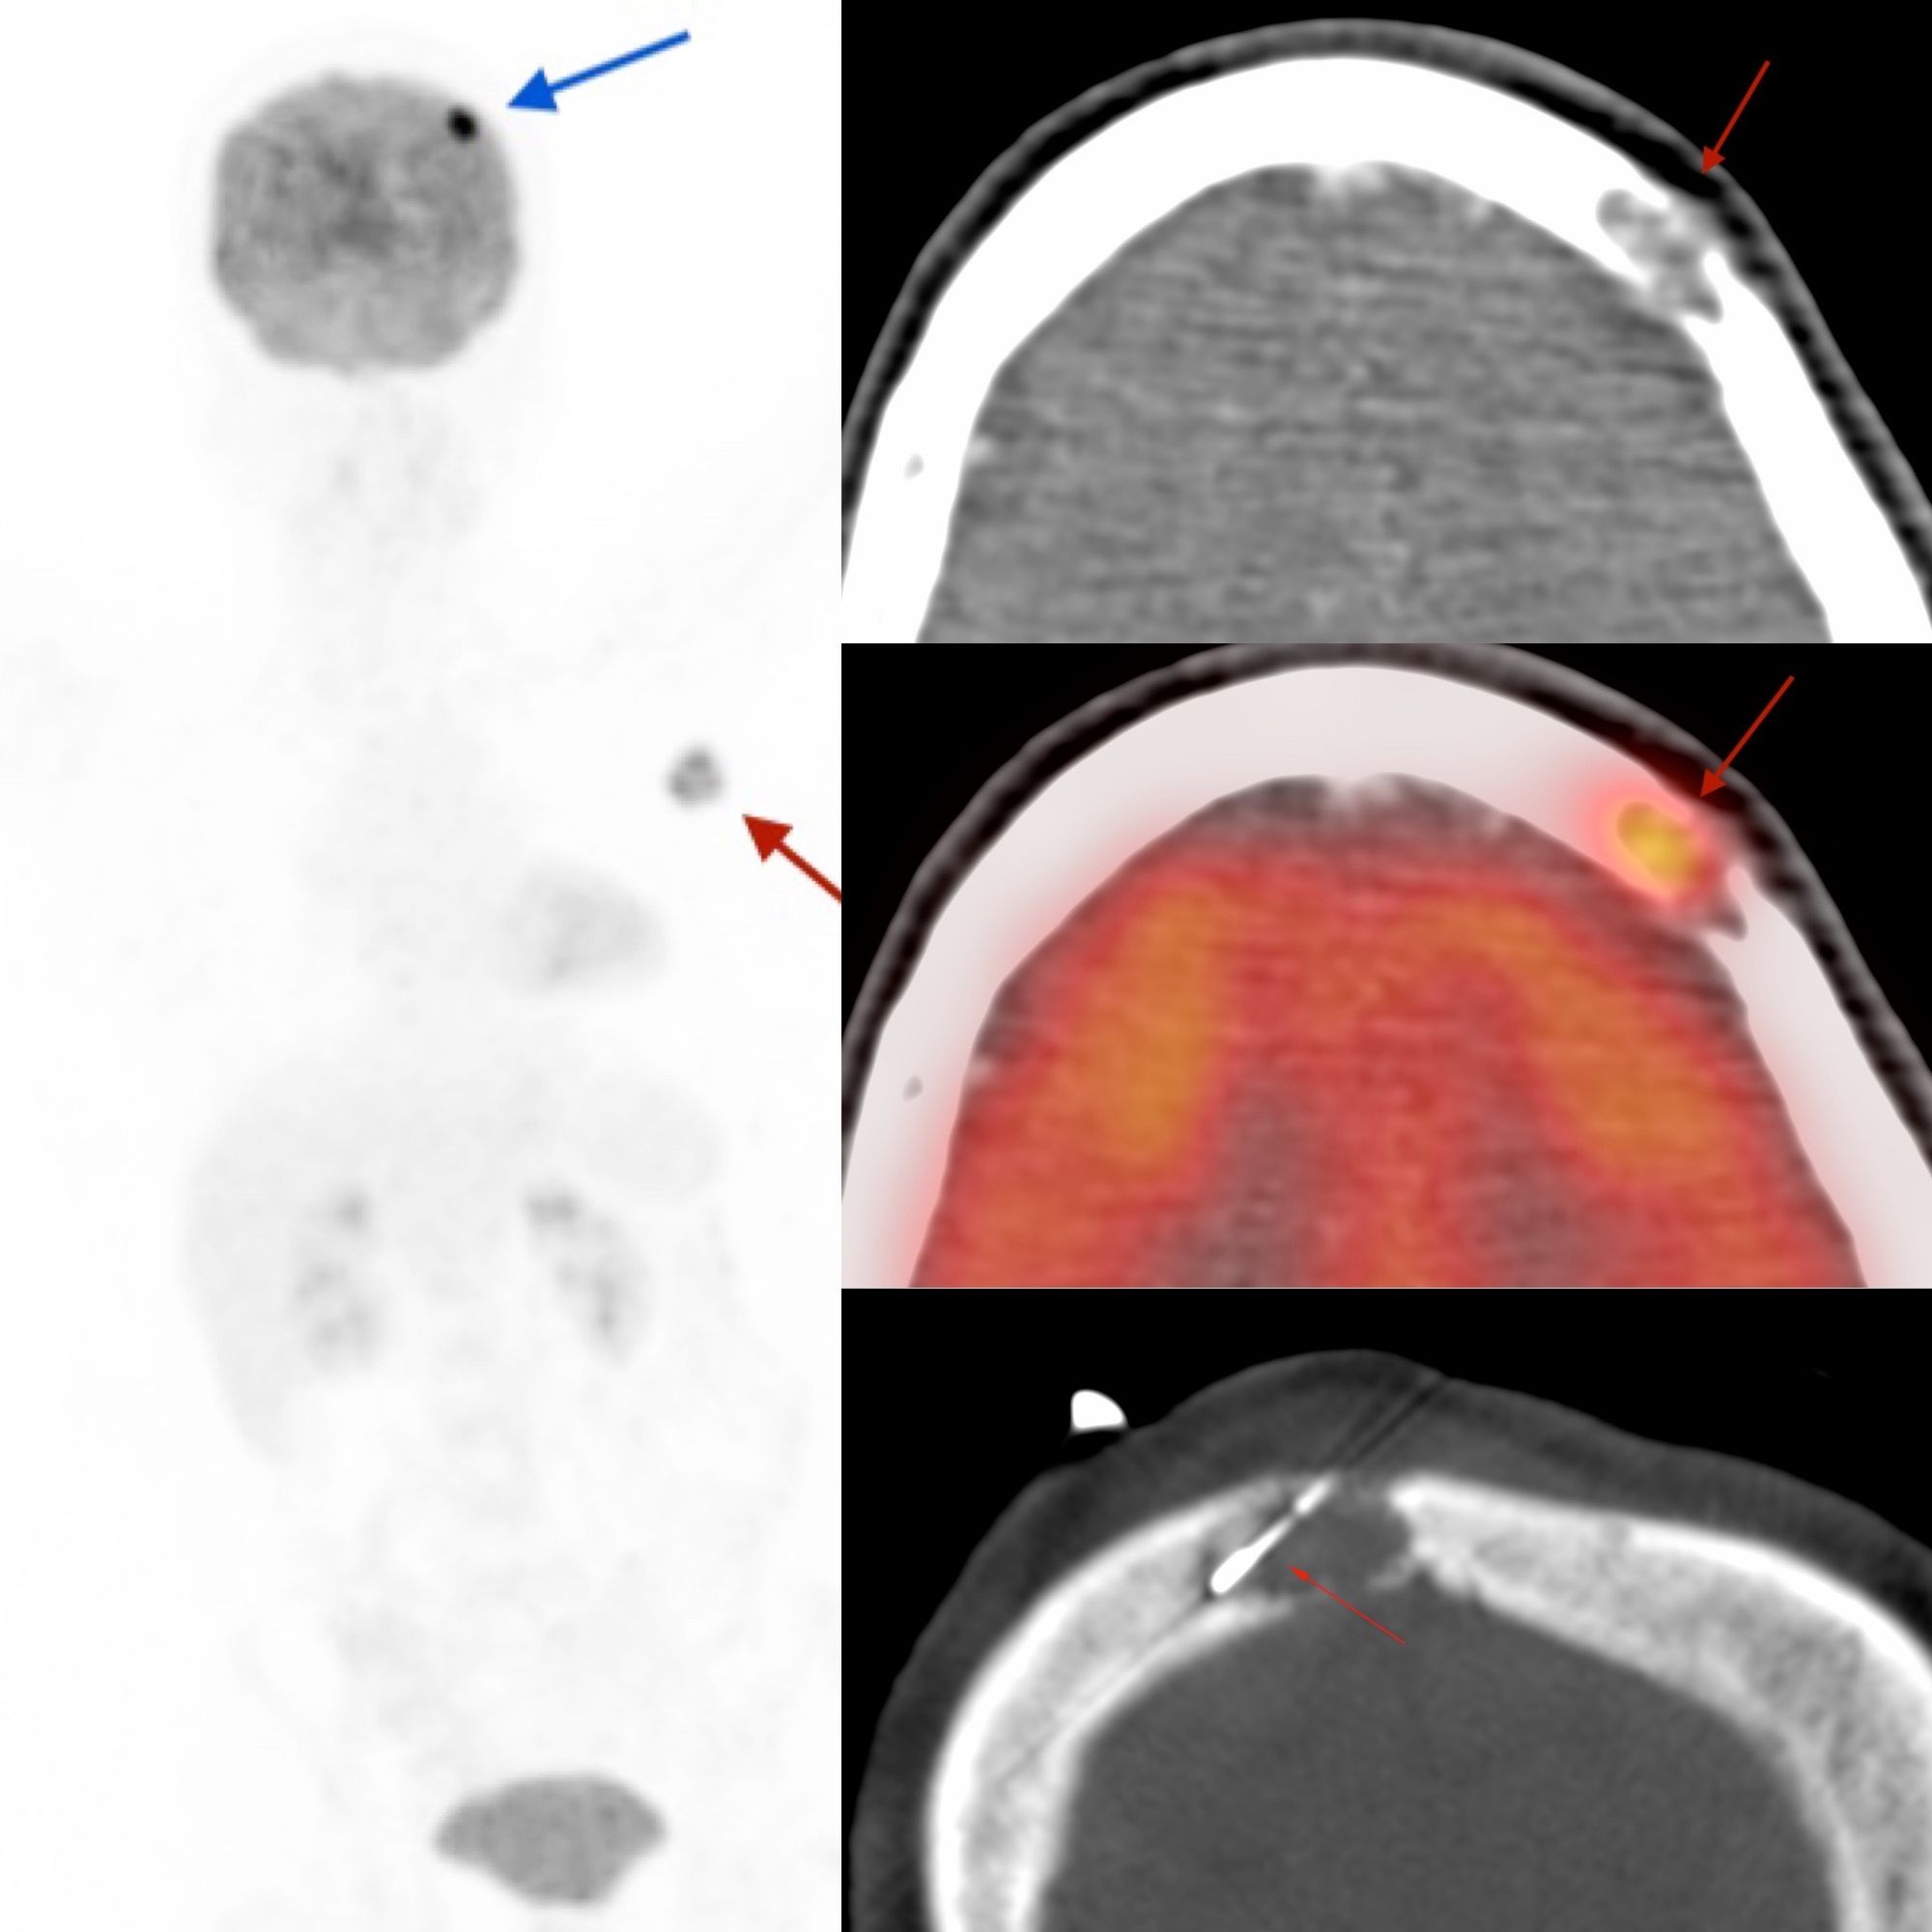

Case 76: When the Biopsy Needle is "Breathed Out" Of the Lesion